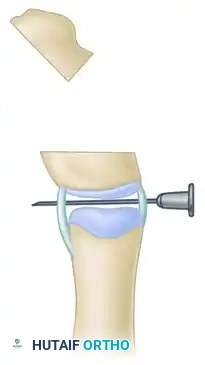

Step G: Osseous Fixation

Secure the realigned bone ends with one or two smooth longitudinal Kirschner wires driven across the osteotomy site and the adjacent joint. These wires are typically left in place for 4 to 6 weeks until radiographic union is achieved.

Late Instability: If a patient presents late with severe instability following a previous failed excision, arthrodesis of the interphalangeal joint is the salvage procedure of choice, providing a stable post for pinch.